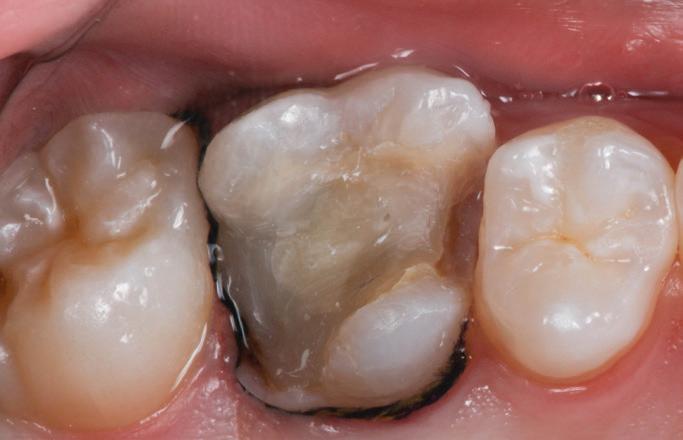

After establishment of local anesthesia and rubber dam isolation, the SSC, the Vitrebond layer, and the Biodentine layer were removed. A hard tissue barrier was found, and an access opening into the pulp chamber was created with a high-speed round diamond bur used with water coolant. Slight bleeding from the visually pale pulp tissue was observed; therefore, CP was performed by removing the pulp tissue from the orifices using a sterile high-speed round diamond bur with water coolant and spoon excavation. The radicular pulp tissue had a resilient texture and bright red blood with continuous flow, suggesting that the pulp was healthy and vital (Fig 9). Next, 2.5% NaOCl was used for pulp wound irrigation, and hemostasis was achieved within 6 minutes by applying cotton pellets soaked in 2.5% NaOCl. Afterward, the pulp tissue and coronal portion of the tooth were irrigated with normal saline solution

Fig 9. Clinical evaluation showing bright red bleeding, suggesting a resilient pulp.